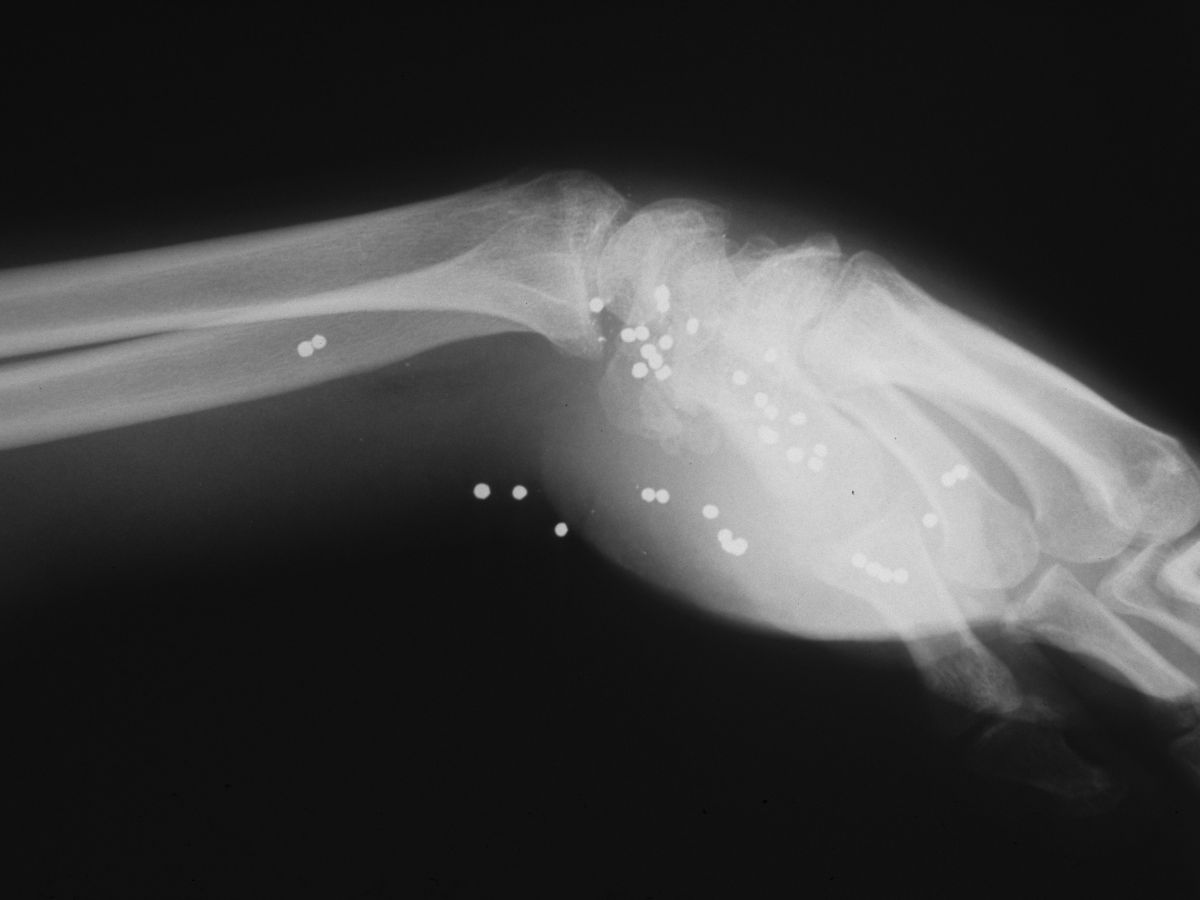

This young adult presented one year after sustaining a close range gun shot injury of his left palm, which had been treated with local wound care. No records were available, and he was vague about the details of the injury. He had complete median nerve loss, a stiff hand and a healed wound in the central proximal palm. Xrays were consistent with retained shotgun pellets, most likely turkey shot (#4 shot, 135 pellets per cartridge).

Postop xrays showing lead debulking.